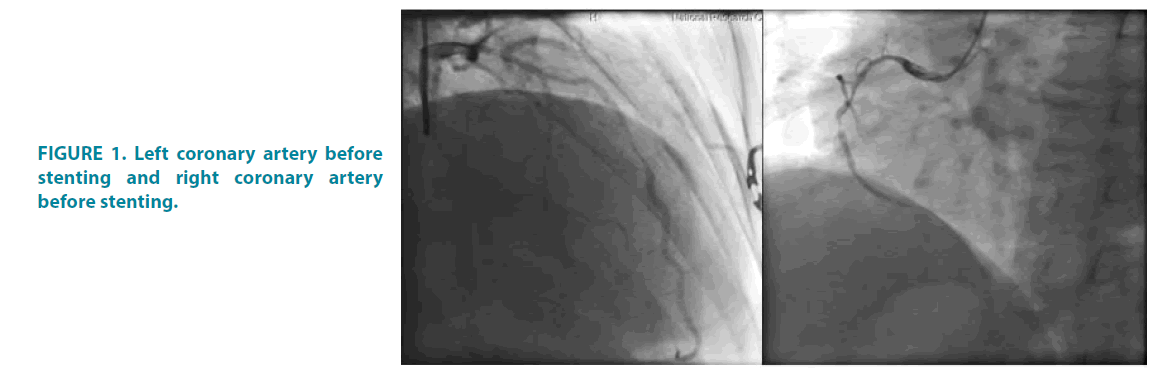

A 72-year-old man was diagnosed at his home with non-ST-elevation acute coronary syndrome (NSTE-ACS) by ECG and clinical signs. The ambulance physicians treated him en route to the hospital with heparin, ticagrelor and aspirin according to our standard protocol. This patient, who was previously unfamiliar to our center, was assessed in the emergency department with a Global Registry of Acute Coronary Events (GRACE) score of 164. We performed urgent coronagraphy, which revealed multivessel lesions of coronary arteries with critical stenosis of coronary artery FIGURE 1.

Figure 1: Left coronary artery before stenting and right coronary artery before stenting.